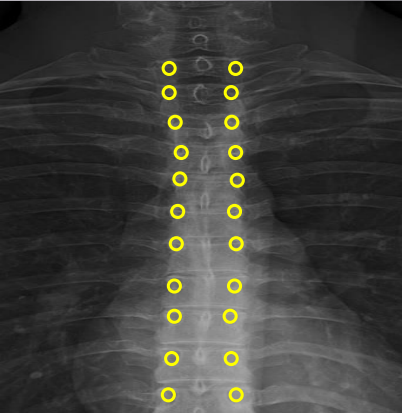

Uncinate processes

Inferior aspect of vertebral bodies

Junction of laminae

Pedicle shadows

Vertebral waist

Inferior endplate tips

Superior endplate tips

Disc spaces

End plate tips